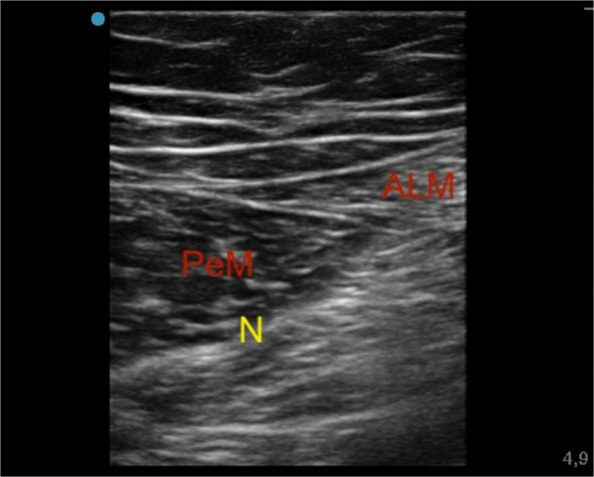

Ultrasound Obturator Nerve Block

Third, being positioned at the patient's groin and surveying the femoral artery and vein, the probe was slid 2–4 cm caudally and then medially until the appearance of the triple layering of the Adductor Longus, Adductor Brevis, and Adductor Magnus muscles. Between these hyperechoic intermuscular septa, the branches of the obturator nerve were identified as flat, oval structures. Once the needle tip was visualized as described above, an anesthetic solution of Ropivacaine 0.375% (dose 9.375 mg) plus Mepivacaine 1% (dose 25 mg) (total volume 5 ml), was injected (Fig. 3).

Fig. 3.

Ultrasound obturator nerve block. Adductor longus muscle (ALM); Pectineus muscle (PeM); Anterior branch of obturator nerve (N)